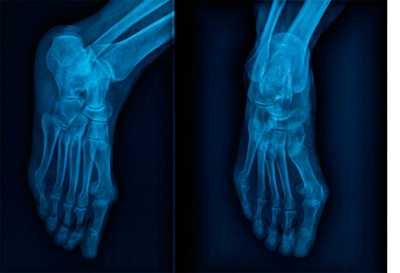

Варианты строения предплюсне-плюсневого сустава на рентгенограмме

Рентгенологическое исследование

Для диагностики повреждения сустава Шопара делают рентген, КТ и МРТ. На передне-задней рентгенограмме определяют величину пяточно-кубовидного угла. Проводят одну касательную к наружному краю кубовидной кости и вторую касательную к наружному краю пяточной кости. В норме угол между касательными колеблется в пределах от 0 до 5°. Увеличение угла свидетельствует о нарушении стабильности пяточно-кубовидного сочленения. КТ во фронтальной и сагиттальной плоскостях позволяет выявить дефект суставных фасеток, смещение костей при вывихе и фрагментацию костей при переломе. КТ, по сравнению с рентгенографией, является более информативным методом диагностики. МРТ позволяет выявить дефекты отдельных связок.